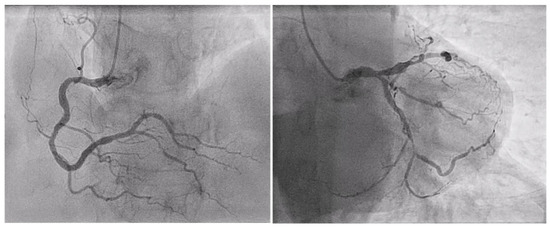

| PCI after Surgery (n° of pts, %) | 10 (72%) |

| Days after Surgery (mean ± SD) | 31 ± 24 |

| LIMA angiographic patency at staged PCI (n° of pts, %) | 10 (100%) |

| PCI during the same hospitalization (n° of pts, %) | 5 (36%) |